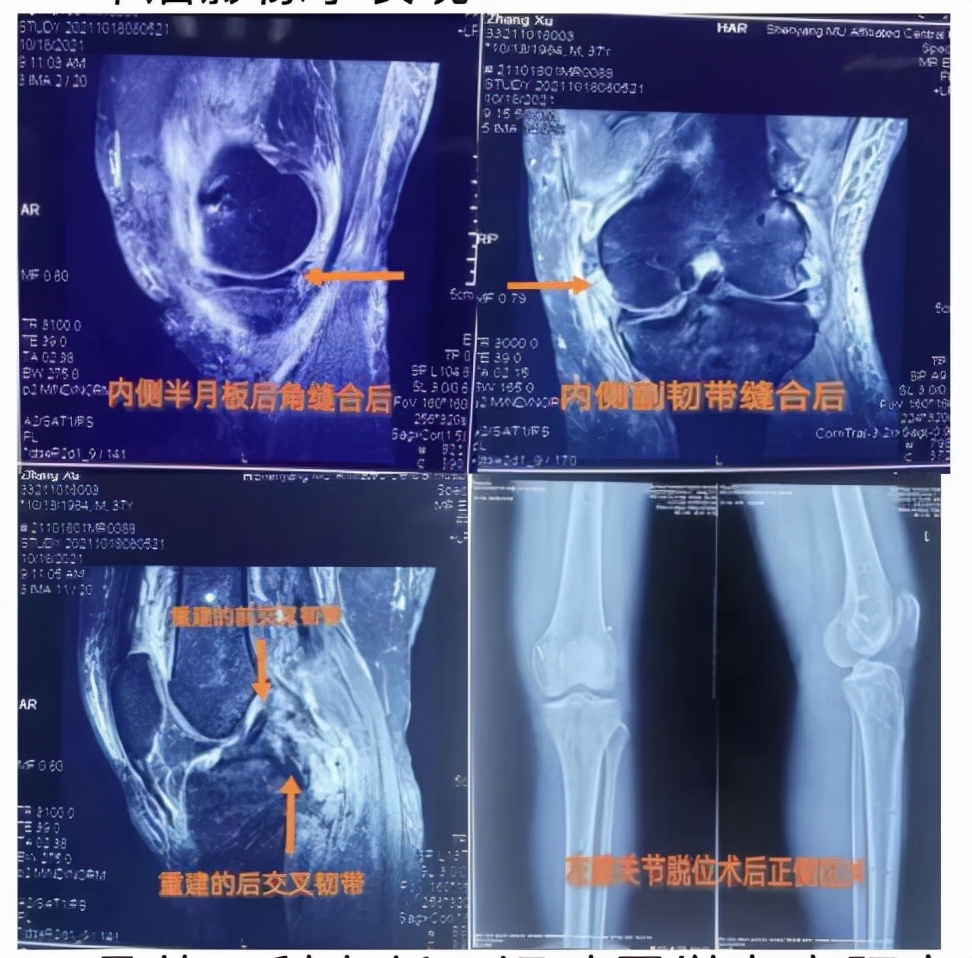

入院后,骨外二科主任、运动医学专家阿良高度重视小张的情况,经过科室团队认真反复讨论,确定了最佳手术治疗方案,急诊给予左膝关节脱位手法复位术,决定二期取自体双侧腘绳肌肌腱对其实施膝关节镜下前后交叉韧带重建术,内侧副韧带修补术,内侧半月板后角撕裂缝合术。手术如期进行,整个团队配合默契,精准操作,完成一个又一个部位的重建,经过近3个小时的持续奋战,手术顺利结束,一次性解决所有损伤,效果非常满意。目前,小张病情平稳,恢复良好,正在逐步加强膝关节功能锻炼,这让他重头燃起了生活的希望,小张及家属非常感激。

术后影像学表现